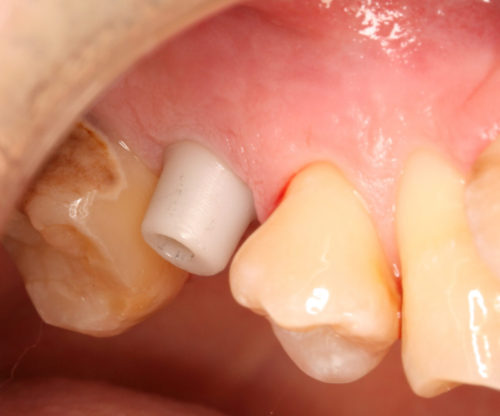

支台装着

土台装着